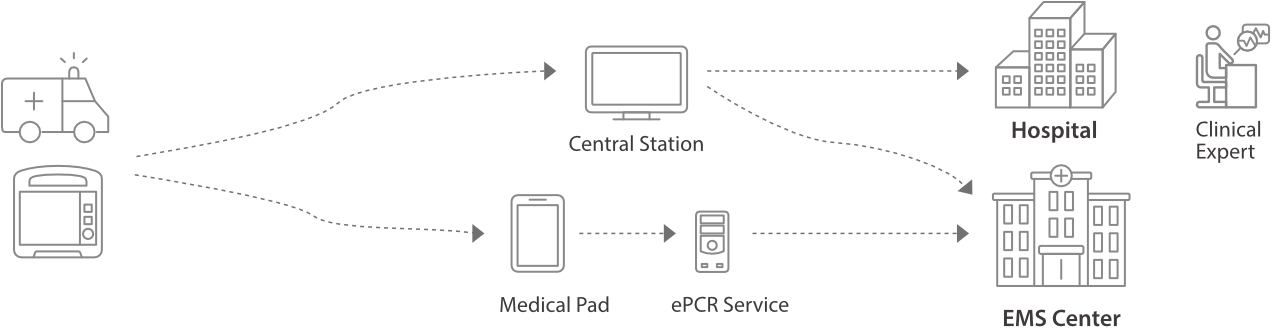

Rettungsdreieck, Umfassender